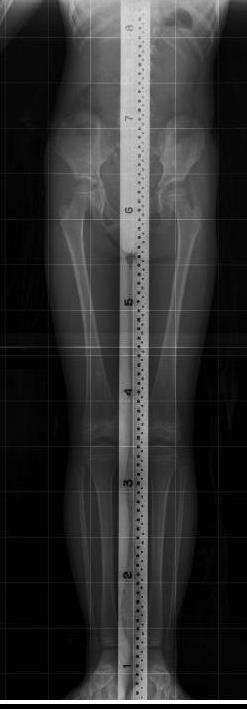

다리길이 차이의 의미

추나요법은 대부분의 다리 길이의 차이가 척추가 틀어져서 생긴 이차적인 현상이라고 봅니다. 따라서 척추가 틀어진 것을 바로 잡아주면 다리 길이는 자연스럽게 맞아 들어 갑니다. 척추를 교정하고 틀어진 관절들이 제자리를 찾아가고 원래의 기능을 회복하면 다리 길이를 굳이 치료하지 않아도 다리 길이는 맞게 되어 있으며 다리 길이가 맞게 되면 치료는 종결 됩니다.